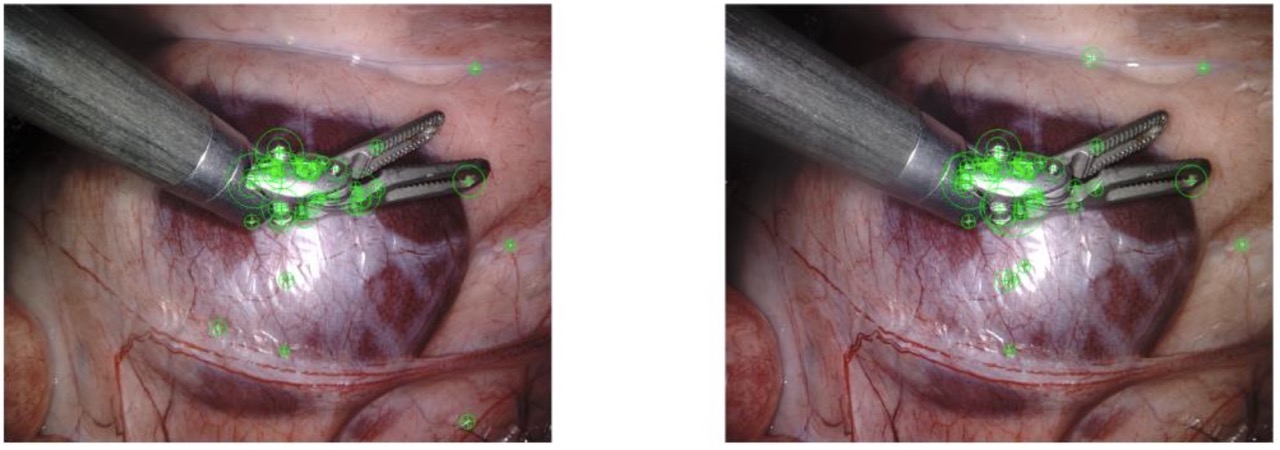

This component focused on reconstructing 3D structure from stereo endoscopic images of a surgical scene:

- Salient Features: Identified keypoints with strong geometric distinctiveness across stereo pairs to support reliable correspondence.

- Stereo Matching: Matched features between stereo views and filtered outliers based on geometric consistency.

- Fundamental Matrix Estimation: Derived the epipolar geometry governing the stereo image pair to constrain valid correspondences.

- Disparity Mapping & Depth Recovery: Generated a dense disparity map and back-projected image points to compute real-world 3D coordinates.